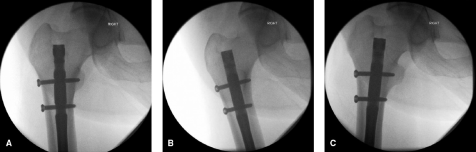

采用翻转侧位投照时,股骨干、股骨颈与股骨头可呈线性排列,使术者能清晰识别矢状面上的细微复位不良。此外,该体位可充分显影内植物在股骨颈及股骨头内的置入情况(图3)。

什么是c型臂术中透视骨科精读 | 股骨近端骨折的转子区域与矢状面力线术中透视技巧_https://www.jmylbn.com_新闻资讯_第3张

图3

▫ 需与翻转侧位联合使用。该投照角度可能难以准确检测矢状面上的细微畸形(图6)。

轴侧位:使股骨干、股骨颈和股骨头呈共线对齐,让术者能够观察到矢状面的细微复位不良。此外,植入物在股骨颈和股骨头内的放置情况可清晰显影。此体位最适用于将植入物定位到股骨头内,但股骨距区域显示不佳。应与标准侧位成像结合使用。